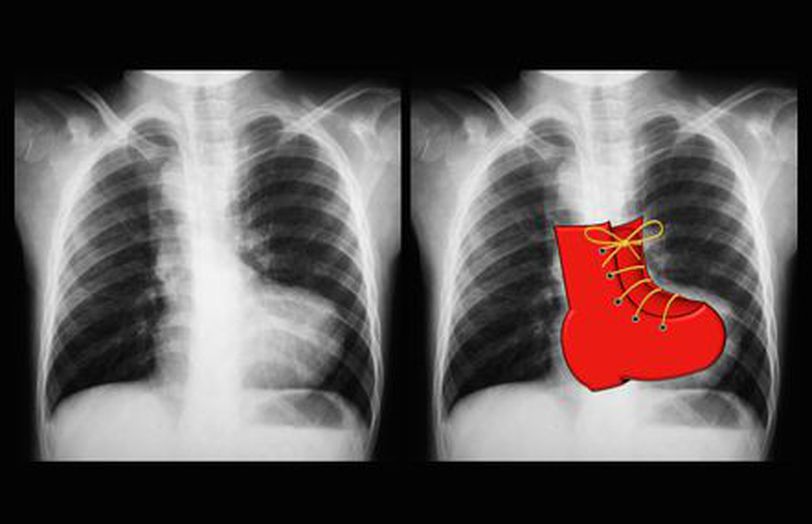

Boot shaped heart

TOF

Tetralogia de Fallot

Blue Baby Heart Defect: Tetralogy of Fallot